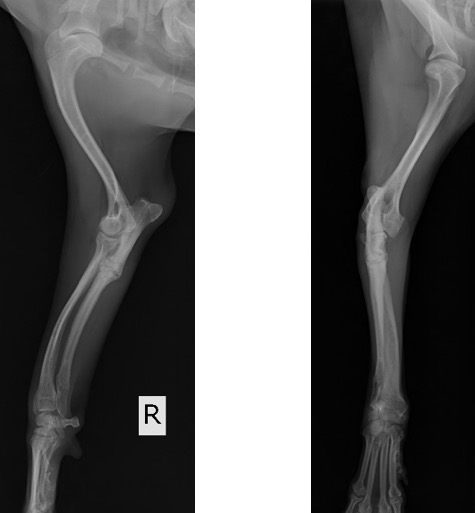

院内においても右前肢の挙上が認められ、単純X線画像検査を実施したところ、右側の橈骨遠位成長板領域の不透過性亢進、肘突起と上腕骨顆の間隙が広がっている所見が認められたため、橈骨遠位成長板早期閉鎖が疑われました。

この症例では、反対側と比較して橈骨の湾曲が顕著でなかったため、肘関節の整合性を優先し、尺骨の骨切りを実施しました。

前腕のLateral像とAP像 (黄丸と黄矢印:成長板の不透過性亢進 赤矢印:上腕骨顆と肘突起の間隙)

術後のLateral像とAP像 (前例と同じく髄内ピンとしてK-wireを刺入したのちに切り取った骨片を破砕し、骨切部分へ再移植しました。)